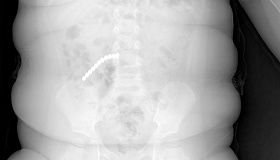

14-сантиметровую ложку проглотил ребенок в Оренбургской области

Происшествия

8 фев, 10:00

10:00